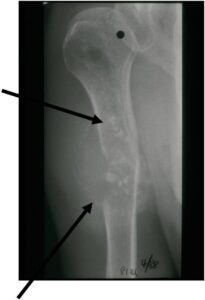

Radiology emulates pathology: Biphasic Tumor

- One region low grade chondrosarcoma

- Second more aggressive area with bone destruction, lysis of calcification, soft tissue mass

- Cortical permeation and a soft tissue mass in 70% of cases

Ill-defined, lytic intraosseous lesion

- Or extraosseous soft tissue mass

- Devoid of calcifications in continuity with lesions having the features of a cartilaginous tumor

Characteristically abrupt transition between chondroid tumor and dedifferentiated, lytic component

Bone may be expanded and adjacent cortex thickened